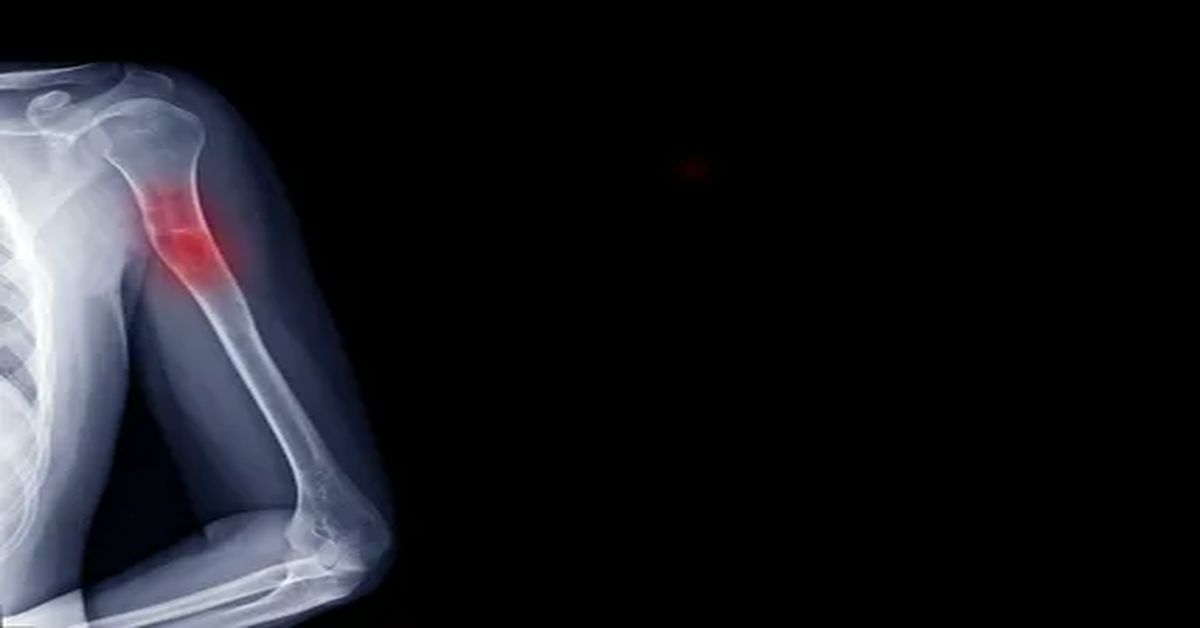

Bu kistler, çoğunlukla uzun kemiklerde görülür. Kol ve bacak kemikleri en sık etkilenen bölgelerdir. Çocuklar ve gençler büyüme döneminde oldukları için risk altındadır. Bazı kistler tamamen asemptomatik olurken, bazıları hafif ağrı veya hassasiyet yaratabilir. Kistin büyüklüğü ve konumu, belirtilerin şiddetini belirler.